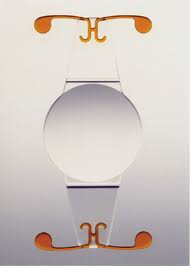

LENS BEING IMPLANTED

3. IOL & related consumables There are multiple IOL choices available for the surgery which are explained below. These lenses can be inserted through a small 1.8 to 2.8 mm opening

Accomodating IOLs These IOLs have flexible hinges that enables them to change focus for different distances hence providing clear distance, intermediate and near vision without glasses.

In this surgery the cataractous lens is broken down into small pieces with the help of ultra sound energy and sucked out. The operation is done through a < 1 mm to 2.8 mm small tunnel incision so that after operation no stitches are required because incision is self sealing. Intra ocular lens is also implanted through the same incision. The foldable lenses are used these days. These lenses get folded and are loaded in a plastic injection. The lens is then injected into the eye through the small incision made for surgery.